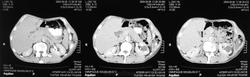

Здесь представлены КТ срезы брюшной полости и таза с контрастированием, выполненные через 2 года после травмы.

Артериальная фаза

на серии кт определяются в средней трети левой почки ,латерально от ее ворот определяется гиповаскулярный участок с четкими ровными контурами .с поддавливанием чашечно-лоханочной системы,ограниченый капсулой почки ,неправильной вытянутой формы ,который в поздней венозной фазе не изменяет своей визуализации (д.д между кистой и кистозной формой почечно-клеточного рака).латерально от левой почки в мягких тканях определяется большой участок со сниженной денситометрической плотностью,размерами - 53х117мм ,с включениями газа и кольцом периферического усиления,с дренажом(вероятнее всего крупный абсцесс).печень увеличена в размере,селезенка с включениями кальция .размеры поджелудочной железы в пределах нормы,холедох и вирсунгов проток без патологии.надпочечники нормальных размеров,без изменений.в области левого тазобедреного сустава определяется участок деструкции с разрушением вертлужной впадины ,головки и шейки бедренной кости ,смещением повздошной кости вверх и латерально на 111.1мм,с фрагментом головки левой бедренной кости .в левой повздошной кости определяются гиперостоз с обширным участком остеосклероза и мелкими участками остеолитической деструкции (смешанный тип).аналогичные остеолитические изменения в крыле правой повздошной кости и в головке правой бедренной кости (сужу по 3d).по медиальному контуру средней трети тела поздошной кости определяется разрушение замыкательной пластинки с вовлечением губчатого вещества на большом протяжении,в крыше и самой вертлужной впадине с мягкотканным компонентом ,с участками пониженной денситометричской плотности (вероятнее всего участки некроза),с мелкими костными фрагментами (что косвенно может подтверждать рост изнутри снаружу),с поддавливанием на большом протяжении органов малого таза,латерально -левая стенка мочевого пузыря утолщена.вывод :такие изменения могут быть как первичного так и метастатического характера .первопричина протрузии возможно врожденного характера(дисплазия) ,затем перелом усугубил процесс(посттравматическая протрузия).меня настораживает тот момент,что изменения в повздошной кости напоминают хронический остемиелит изначально .а затем появились изменения ,сильно напоминающие озлакочествление+изолированно крупный абсцесс